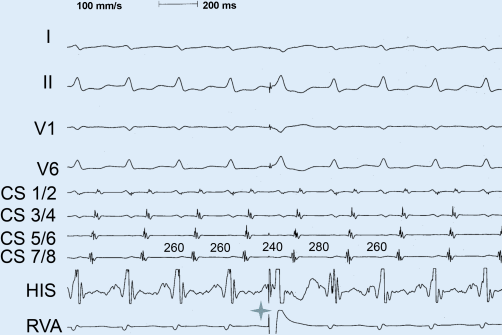

AV-Reentry-Tachykardie und Wolff-Parkinson-White-Syndrom | Herzschrittmachertherapie + Elektrophysiologie